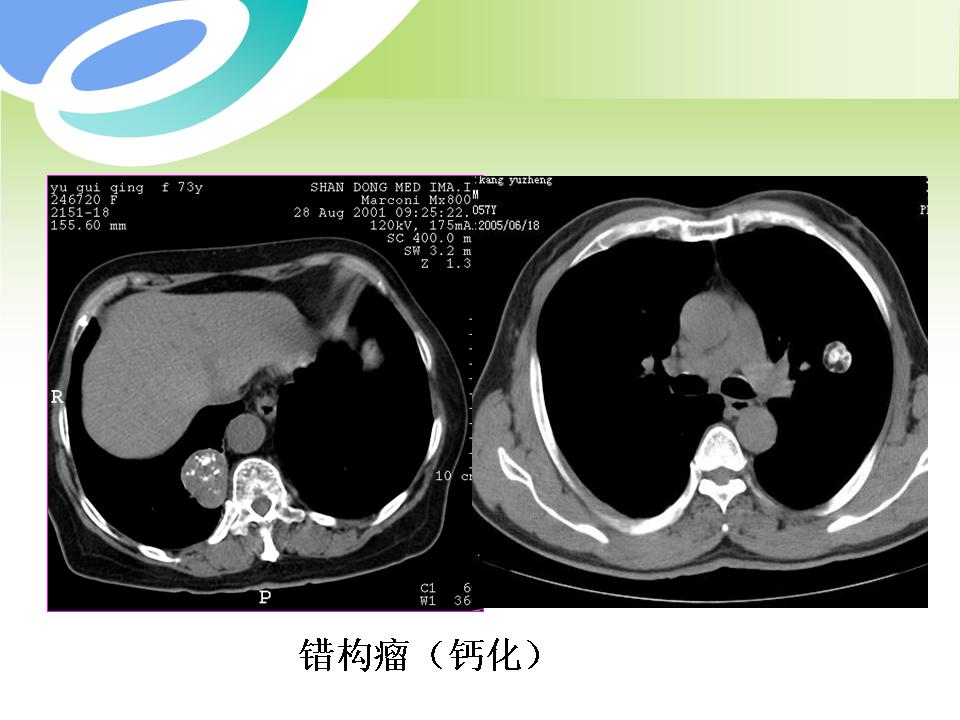

肺部病变的CT基本征象